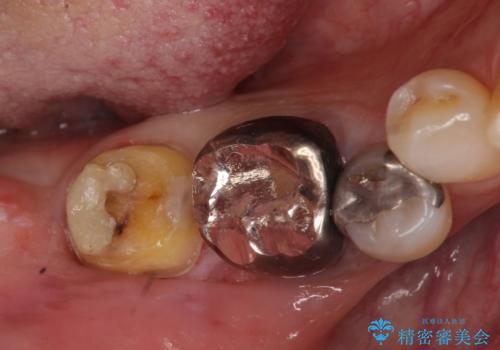

- 右下奥の銀歯の下が虫歯になっていました。

歯ぐきの下までしっかり修復するために、歯周外科手術を含めた治療を行いました。

歯ぐきの中まで虫歯の場合は、まず、虫歯も取りきることが難しいです。

また、被せ物のきわを歯ぐき深くに設定してしまうことになり、正確な歯型がそのままでは取れません。また、歯ぐきのみを取り除いても一時的な処置となり、また歯ぐきが再生してしまうため、最終的には歯ぐきの腫れが治りません。